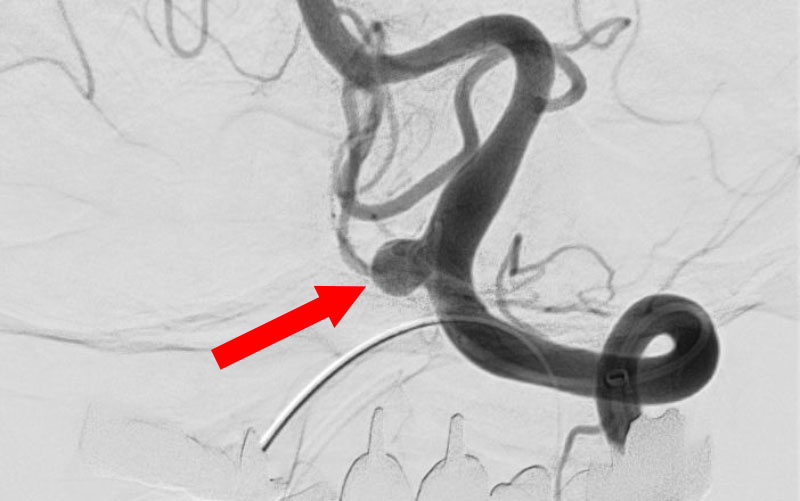

'26年4月

前交通動脈瘤

50代

大阪府の病院

No.1627 手術前

No.1627 手術中

No.1627 手術後